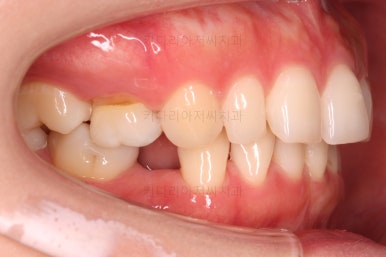

두번째 치료를 시작합니다.

이번 치료의 목표는 공간을 좀 더 재분배하고요.

부족한 교합을 맞추고 정중선을 맞춰나가야 합니다.

미니스크류는 필수로 사용되고요.

장치 착용 모습인데요.

교정 중임에도 불구하고 거의 눈에 띄지 않는다는 압도적인 장점이 있죠.

공간, 교합, 중앙선 모두 매우 좋아지고 있습니다.

윗니 한 쪽만 왜소치여서 100% 중앙선을 못맞추는 건 환자분 본인도 잘 아시는데요.

그래도 할 수 있는데까지 해보기로 했습니다.

역시 얼굴모습을 자주 확인해 주고요.

중앙선도 처음보다 매우 좋아진 양상입니다.

옆모습도 큰 변화없이 양호하게 진행중이고요.

디테일을 위해서 세번째 치료까지 진행이 되었고요.